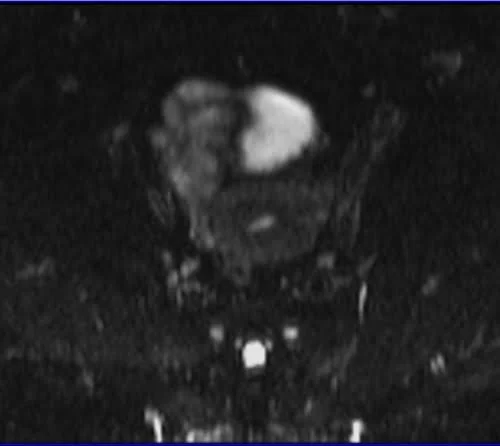

A diffusion-weighted (DW) axial fat-saturation sequence with b-factors of b0 is used in female pelvic imaging.

A diffusion-weighted (DWI) axial fat-saturation sequence with b-factors of b500 is used in female pelvic imaging.

A diffusion-weighted (DWI) axial fat-saturation sequence with b-factors of b1000 is used in female pelvic imaging.

ADC MAP OF B0,B500 AND 1000